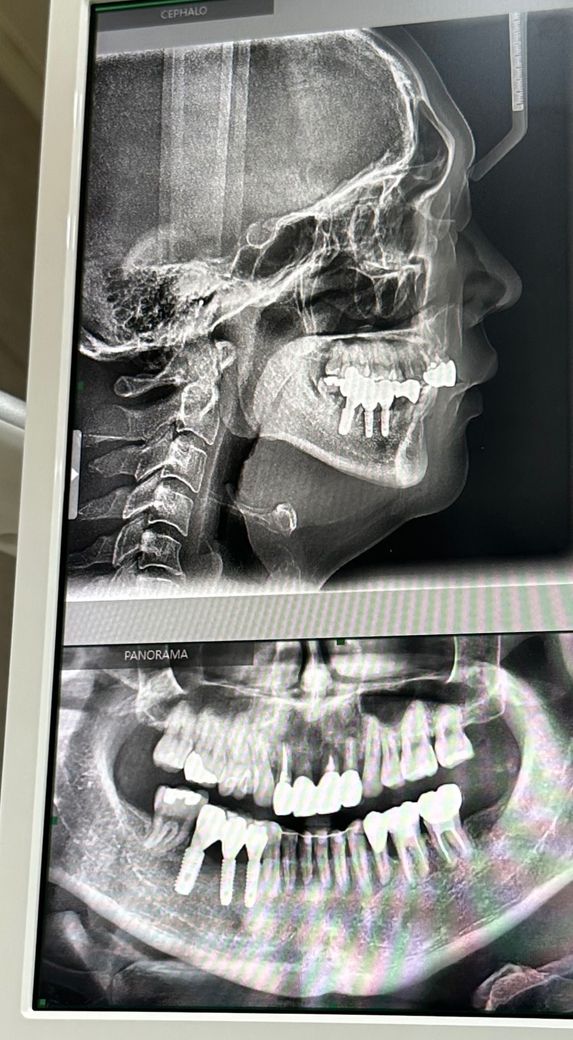

앞니 잇몸이 내려가고있어요 뽑힐까요?

30대후반 남성 교정후7년지남

전체적으로 치아뿌리가 짧고 잇몸이 안 좋아 교정이후 관리를 열심히 해도 전체적으로 잇몸들이 내려가고 있습니다 위앞니는 버티다가 임플란트를 할생각인데 밑에 앞니까지 잇몸퇴축이 와서 빠질까봐 걱정이에요

• 1번 째 사진

엑스레이 사진으로 정확히 알수는 없으나 관리를 잘하신다면 충분히 오래 사용하실 수 있습니다.

엑스레이 상으로는 아직은 그정도는 아니니 관리를 잘하시면 크게 문제가 되진 않을것같습니다.

말씀하신 것처럼 교정 이후 치근 흡수가 진행되어 다소 짧으면서, 잇몸 상태도 좋지 않아 여러모로 불리한 상황입니다.

다만, 잇몸뼈가 많이 퇴축되어 치아가 흔들린다고해도 그냥 막 일상생활하다가 빠지진 않습니다.

현 상태에서 더 악화되지 않도록 잇몸치료하면서 꾸준히 관리해주는 수 밖에 없습니다.